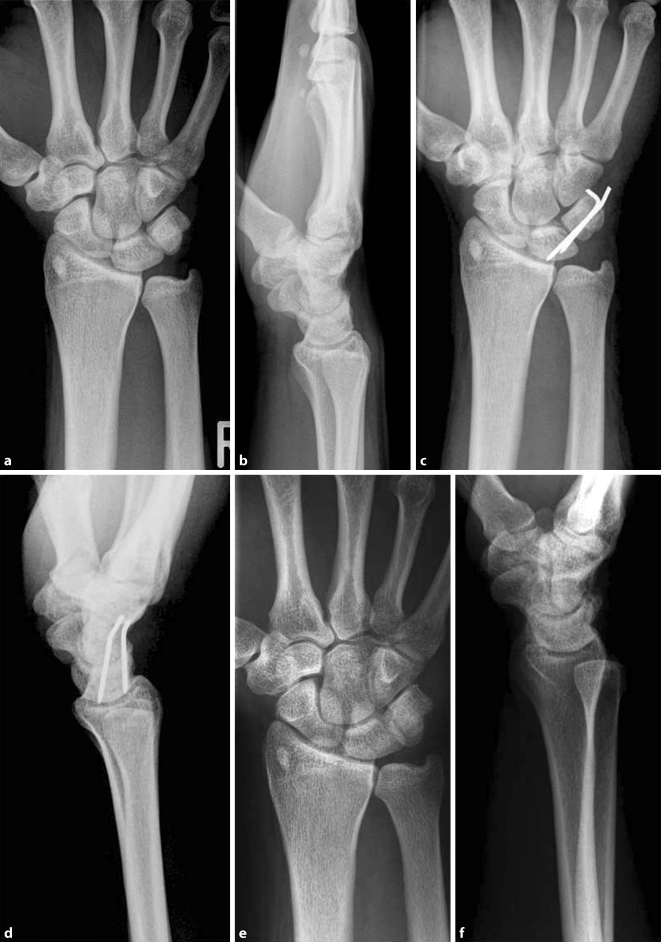

Arthrose Der Hand Und Fingergelenke Obere Extremitat